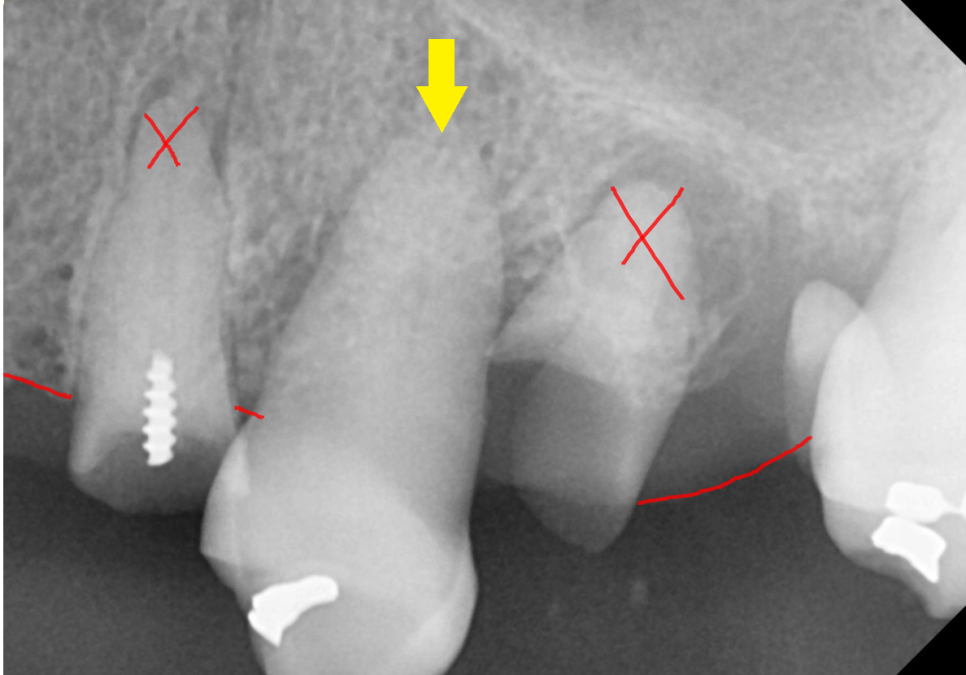

전체적인 치아 치료가 필요할 경우 진단 과정에서

살릴 수 있는 치아와 없는 치아를 분리하게 됩니다.

< 진단 과정 >

치아가 남아 있어도

x-ray를 찍어보면 잇몸뼈가 다 녹아

허공에 떠있습니다.

이런 경우는 발치가 필요하고요~

뿌리가 튼튼하고

잇몸 뼈가 녹지 않아 흔들리지 않는 경우는

살릴 수 있습니다.